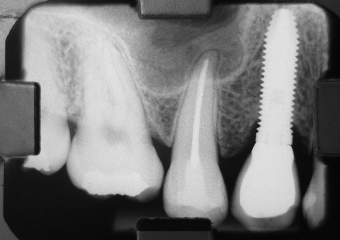

Raio X Inicial

Rx e imagem da prótese fixa em porcelana sobre implante